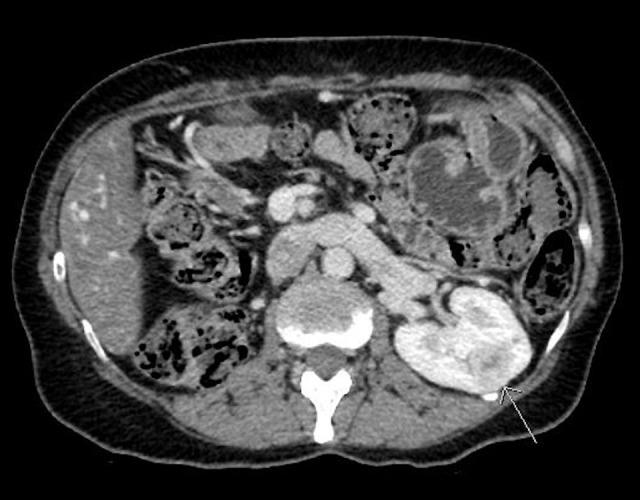

BACKGROUND One-third of renal cell carcinoma cases present with an initial metastasis to various organs, emphasizing the tumor's unpredictable behavior. Prognosis is poor once metastasis is discovered. Multiple-organ involvement with metastatic lesions has a particularly dismal survival rate. Surgical resection alone of metastatic masses can extend patient survival with reasonable quality of life. CASE REPORT Here, we present the case of a healthy 46-year-old woman who initially presented with an incidental localized clear cell renal cell carcinoma. During the follow-up period, she presented with sequential asynchronous metastasis to the pancreas, thyroid, skin, contralateral kidney, and lung. She has no family history of malignancy. Her physical examination and laboratory investigations were normal even upon presentation of most of her metastatic organs. The first metastasis was in her sixth year of follow-up. She underwent consecutive metastasectomy of all the organs described above, excluding the lung. She eventually was started on sunitinib after non-resectable lung nodules were discovered. Her survival is now over 10 years since her first metastasectomy, with good performance status. CONCLUSIONS Metastasis to a single organ has a poor prognosis and dramatically affects survival. Nevertheless, our patient had multiple consecutive examples of metachronous metastasis, yet she has survived for over a decade since the occurrence of metastasis. Our case offers more information to fill the gaps in understanding the favorable role of surgical resection in advanced renal cell carcinoma metastasis.

背景